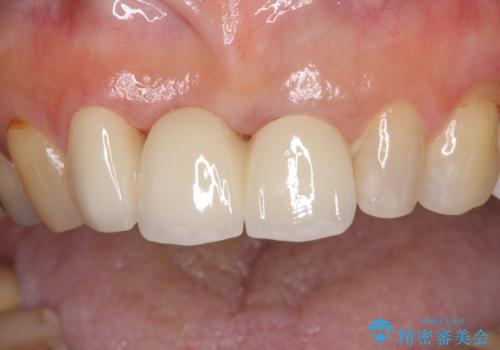

折れてしまった前歯 オールセラミックブリッジで自然な口元に

折れた前歯を抜歯すると、歯肉が痩せてしまい、ブリッジの形態の審美性が失われることがあります。仮歯を調整することで審美回復が必要であるか判断しますが、今回は歯肉移植を行うことなく補綴治療を行いました。